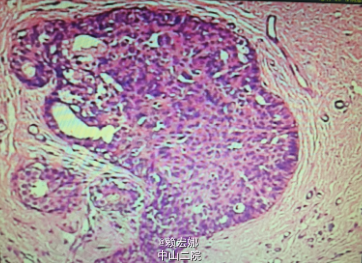

曾在局麻下行B超引导下右侧乳腺肿物穿刺活检术 +右侧腋窝肿物穿刺活检术,原发肿物:右乳12点钟乳晕旁见一大小为2.5*2.1cm的实性低回声团,右侧腋窝淋巴结3.5*1.9cm,术后病理:(右乳肿物、右腋窝肿物穿刺)乳腺浸润性导管癌,Ⅲ级。免疫组化:ER(-)、PR(-)、Her-2(3+)、Ki-67(+,40%)、P63(-)、E-cad(+)、Calponin(-)。

右侧乳腺癌诊断明确,予以TE新辅助化疗三次后,复查彩超:右乳12点钟乳晕旁见范围约1.4*0.9cm的实质性低回声团,边界不清,右乳10点钟方位见一大小为0.7*0.3cm的实性低回声团,边界清,形态规则,提示:1.右乳实性占位,多考虑乳腺Ca可能(较前次检查明显缩小);右乳实性低回声团,多考虑增生结节可能(BI-RADS Ⅱ类);双侧乳腺符合乳腺增生征象;2、双侧腋窝见淋巴结(右侧部分淋巴结淋巴门偏心)。患者经新辅助化疗后肿物明显缩小。患者完善相关检查,无明显手术禁忌症,遂在全麻下行右侧乳腺癌改良根治术+前哨淋巴结活检术,术后病理:1、(右侧乳腺浸润性导管癌癌灶剔除术后)残腔未见癌残留;2、乳腺及皮瓣四侧切缘,基底边缘及乳头未见癌浸润;3、(前哨、腋窝)淋巴结未见癌转移(0/3、0/14)。